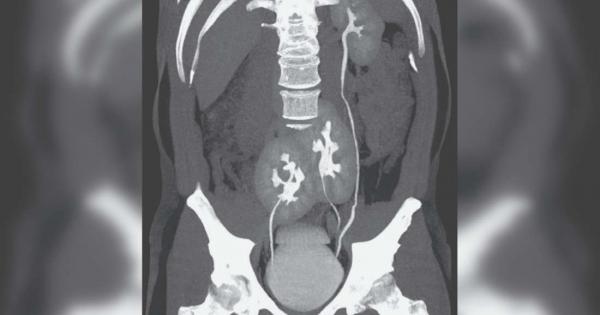

... когато примитивните и подобни на бъбреци структури се разделят на две. Въпреки че е изключително рядко, подобно състояние е било документирано няколко пъти преди. Източник: IFLScience